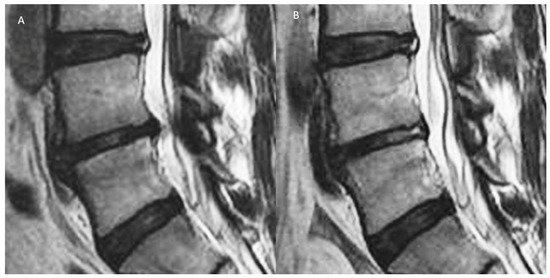

11.2. Clinical and Radiological Factors Predictive of Conservative Failure